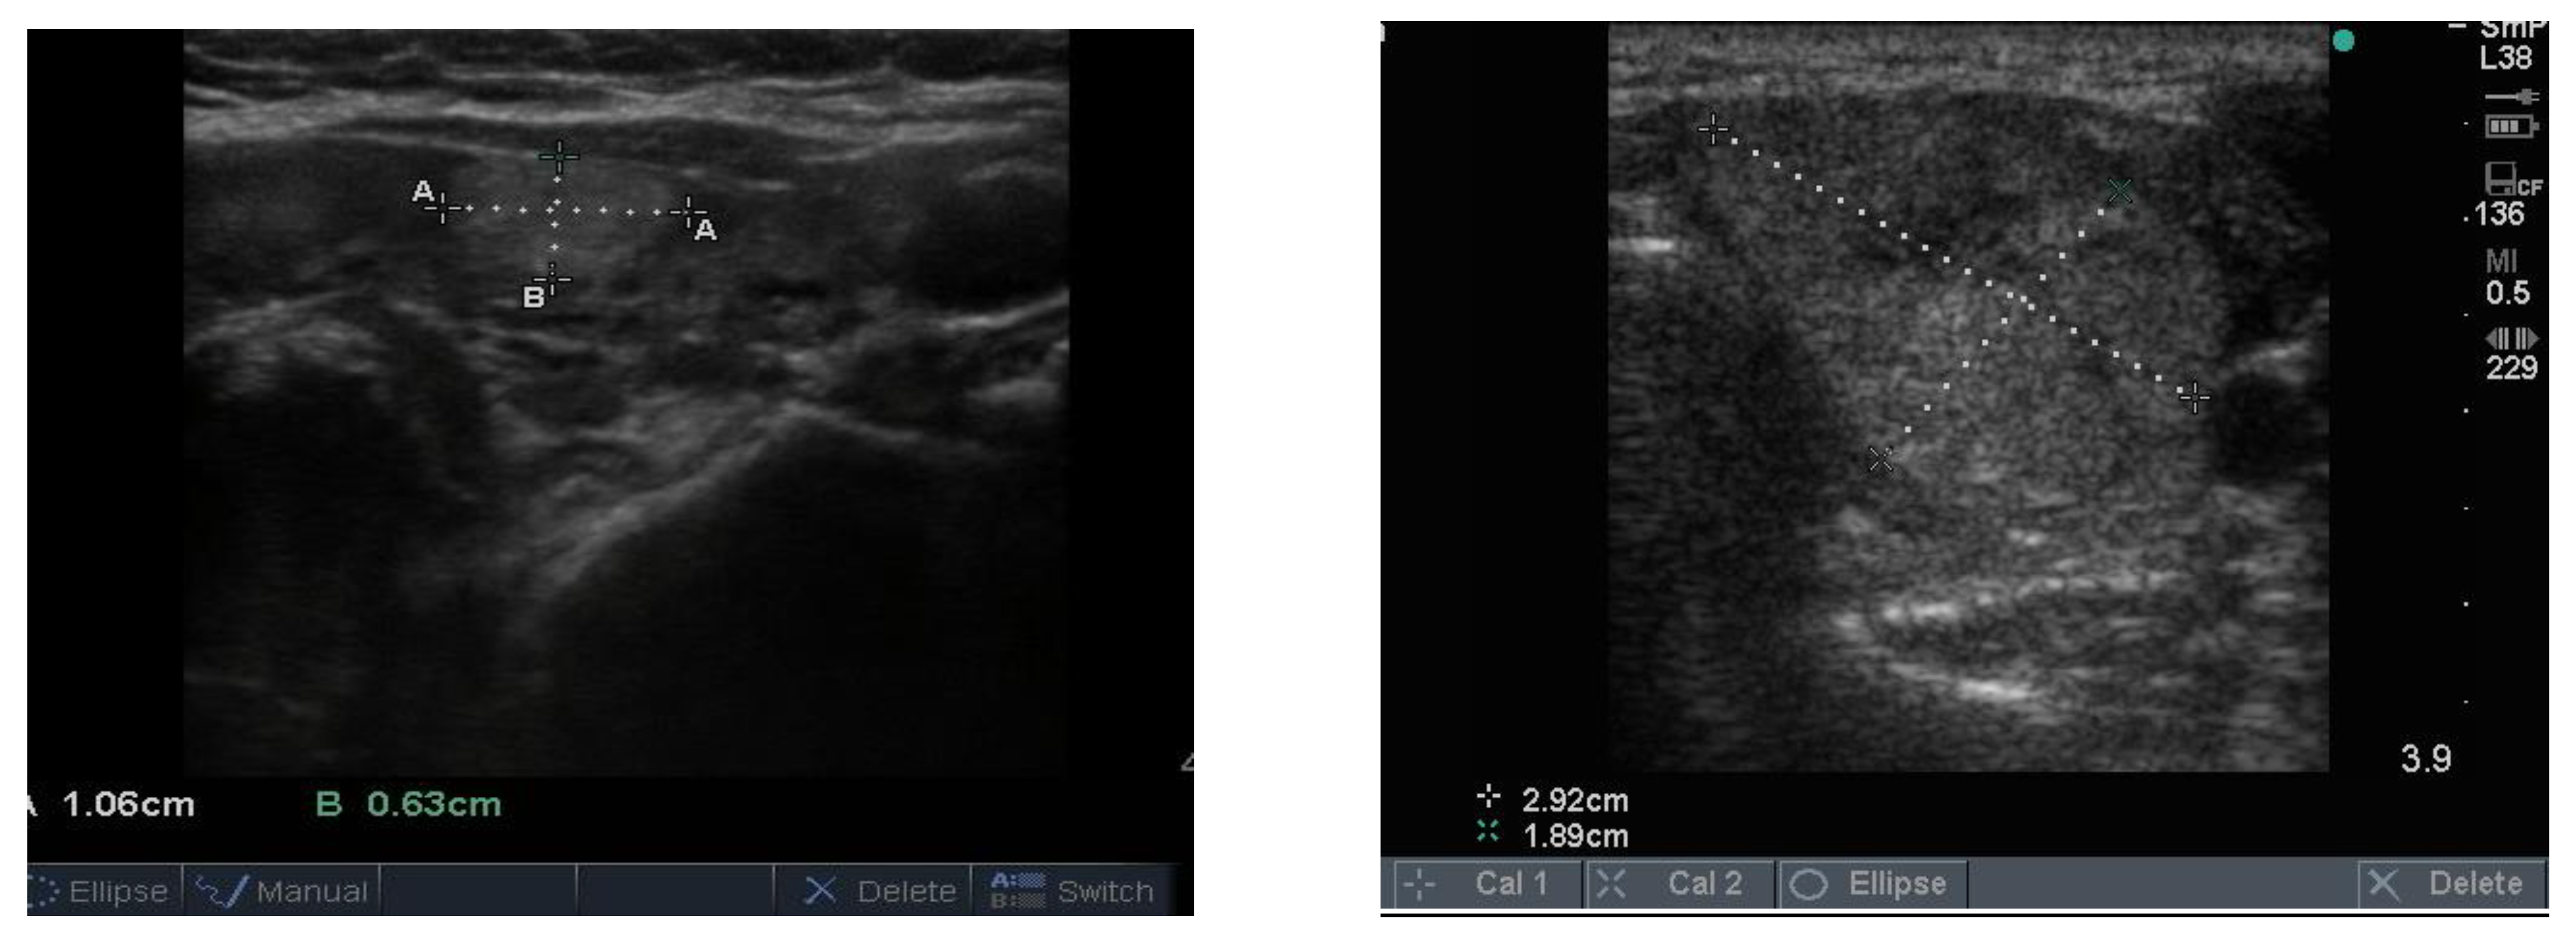

Follicular nodules are much less common than colloid nodules with a different appearance on ultrasound; they are more cellular, giving a solid appearance, with a whitish colour, i.e., less hypoechoic. They too have a sharp edge and halo and grow slowly over time [5]. The problem with these lesions is that FNAB is unable to differentiate between a benign follicular adenoma and follicular cancer, and if the latter is suspected, thyroid surgery is the final arbitrator. About 10% of benign thyroid nodules are follicular, and most of them end up being removed. Two examples of follicular nodules that were finally proven to be benign are shown in Figure 4. On follow-up ultrasound (US), 6–12 months later, repeat biopsy might be indicated if a nodule has grown by 20% or more in two or more dimensions; benign nodules also grow, but less quickly.

Figure 4.

Two examples of follicular nodules that were shown at surgery to be benign. The nodules are roughly oval shaped, slightly hyper echoic and have sharp edges and, particularly, the bigger of the two, thick halos.